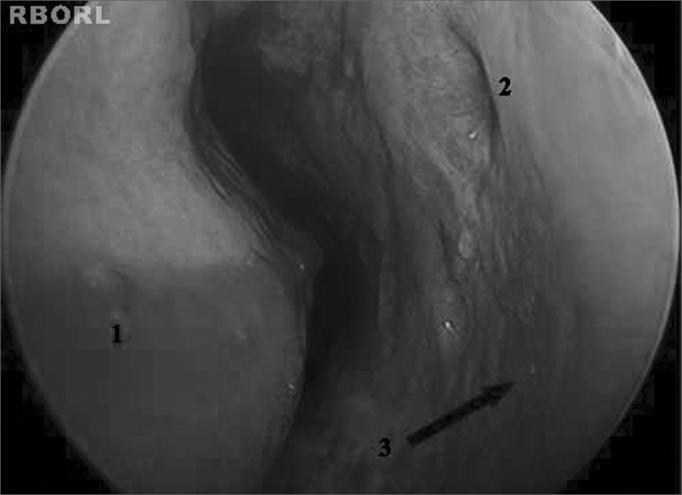

This retrospective study looks into patients on mechanical ventilation with fever of unknown origin and signs of rhinosinusitis on CT images who were submitted to inferior meatus maxillary sinus puncture.

The total study sample consisted of 27 patients (70.3% male; mean age 45.3 years). The most common Intensive Care Unit admission diagnoses were head trauma and stroke. CT scans revealed the maxillary (85.2%) and sphenoid (74.1%) sinuses were the most involved paranasal sinuses. Middle meatus purulent drainage was seen in 30.7% of the nasal cavities. Fever was reduced in 70.4% of the patients after puncture (p < 0.001). The most commonly found organisms in sinus aspirates were Pseudomonas aeruginosa and Acinetobacter baumannii.